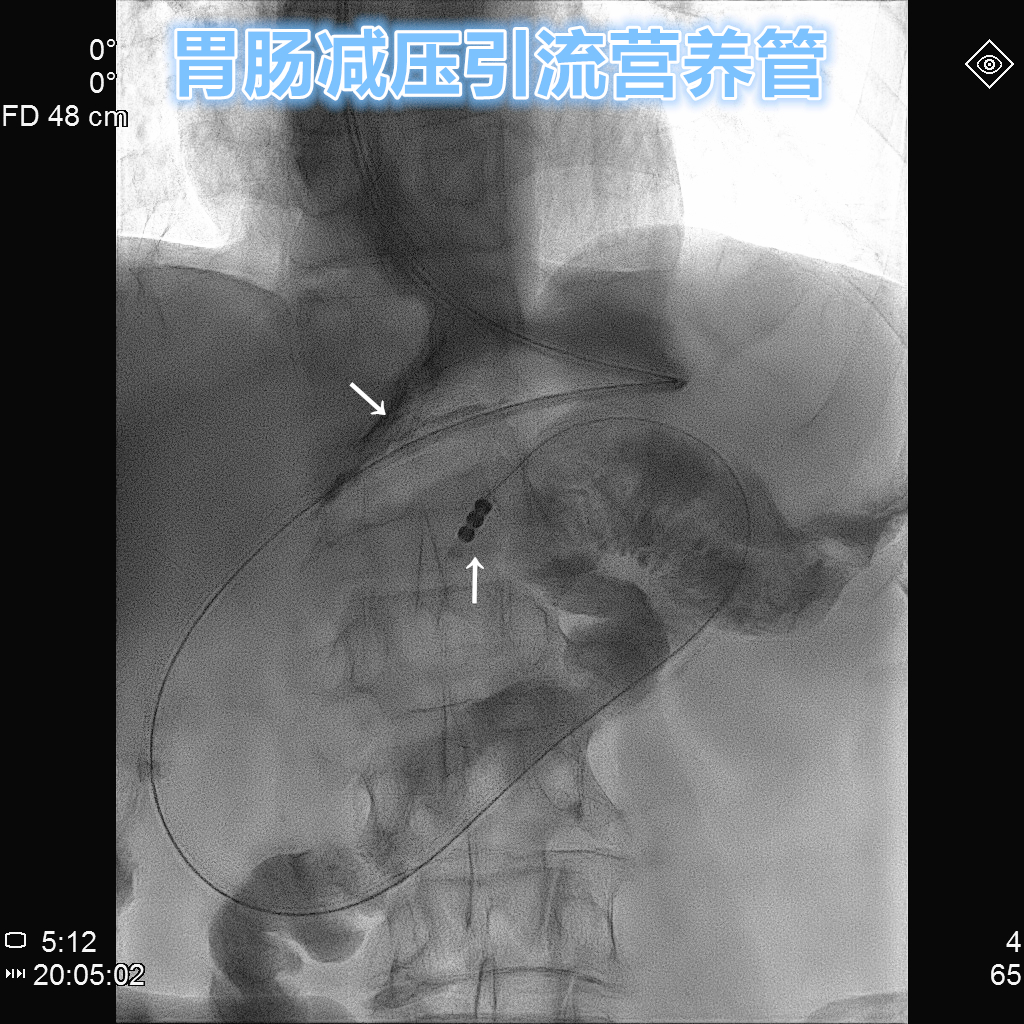

胃肠减压引流营养管

- 例1

老年男性,早期胃癌术后,术后出现顽固性胃瘫,又无法耐受长期静脉营养支持治疗。采用胃肠减压引流营养管,不仅大大提升舒适度,而且有多侧孔使得减压引流效率更佳!